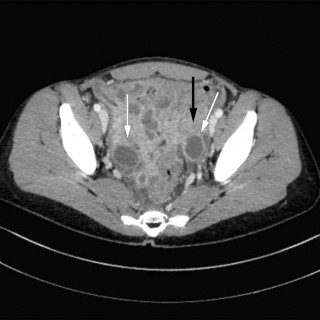

En mann i 50-årene ble brakt bevisstløs til akuttmottaket, hvor det ble påvist forhøyet osmolalt gap og aniongap. Pasientens promille på 2,1 kunne forklare det forhøyede osmolale gapet, men neppe bevisstløsheten eller det økte aniongapet. Årsaken til bevissthetstapet ble påvist først fire timer etter innleggelse, og det kliniske bildet var atypisk. En mann i 50-årene ble funnet bevisstløs utendørs. Ambulansen ankom fire minutter etter varsling, og pasienten hadde da GCS-skår (Glasgow Coma Scale) på 3, snorkende respirasjon, normal respirasjonsfrekvens (18 pust/min) og ikke målbar SpO 2. Han...